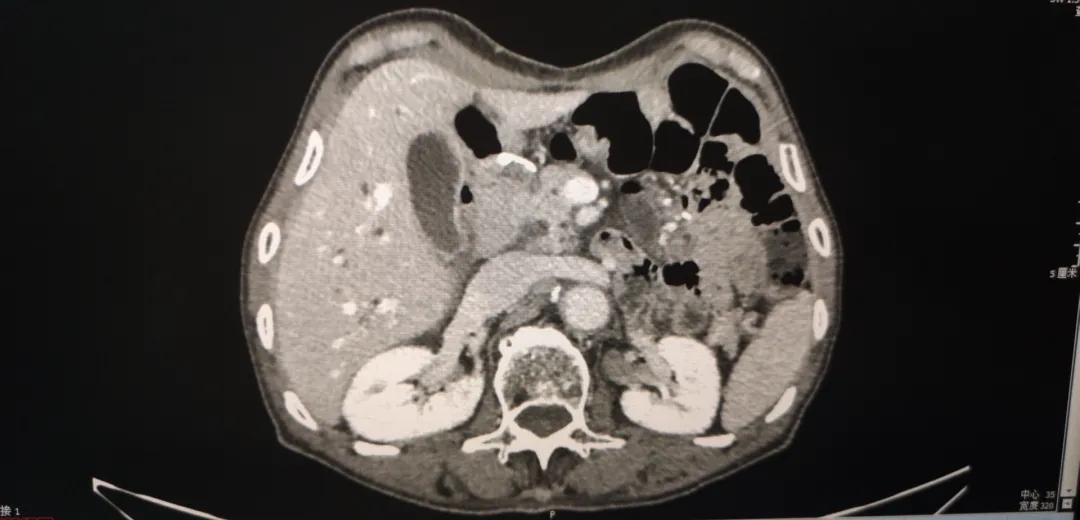

2020-4增强CT:与2019.11.25腹盆片比较,整体未见明显变化。

2020.4腹盆CT

2019-11 腹盆CT